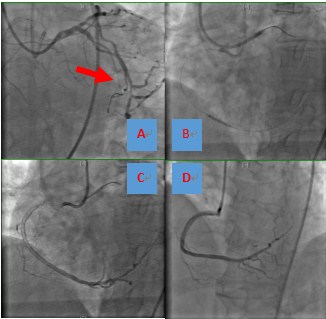

正常情况下,左右冠状动脉之间的侧支循环(collateral connections,CC)处于功能性关闭状态,在冠状动脉造影时并不显影,仅在冠心病患者有至少1支主要冠状动脉狭窄>75%,方可开放而发挥作用。CTO病变时,侧支血管血流量可以达到正常冠状动脉血流量的50%-80%,从而为闭塞血管供血区域的心肌提供氧和营养。在反复尝试从闭塞的右冠状动脉开口置入导丝失败后,在王伟民教授操刀下,采用逆向导丝技术,沿左回旋支发出的侧支血管逆向(指逆RCA的血流方向)成功到达闭塞的右冠状动脉开口,在左右冠状动脉之间架起一座“鹊桥”,随后的支撑导管从右冠状动脉开口沿逆行导丝顺利进入右冠状动脉,随后球囊扩张植入支架,完美的开通了闭塞的右冠状动脉,恢复右心室心肌血流供应,如图2所示。

图2 逆向导丝技术.A至D,导丝沿左回旋支发出的侧支血管逆向(指逆RCA的血流方向)成功到达闭塞的右冠状动脉开口,随后的支撑导管从右冠状动脉开口沿逆行导丝顺利进入右冠状动脉,接着球囊扩张闭塞血管,并植入支架,完美的开通了闭塞的右冠状动脉,恢复右心室心肌血流供应。